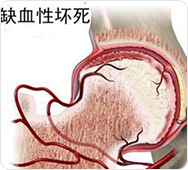

股骨头周围血液供应遭到破坏,骨细胞无法得到充足的营养供应,会慢慢“饿”死,由于股骨头周围血供中断,药物很难顺利到达病灶发挥疗效;而原先通过正常血液为骨细胞提供的营养也被阻拦下来,最终导致药物、营养进不去。

同时,由于血运不通,骨髓内压和关节腔内压增高,不断刺激股骨头软骨和滑膜产生炎症、积液,坏死的骨质游离在关节腔内,关节腔内代谢产物出不来,最终形成恶性循环,股骨头病灶部位将如同缺水的庄稼,最终枯死。

保障股骨头有利生存环境;关节腔内炎症、积液、游离物质若不清理干净,将会进一步侵蚀骨质;

促进新骨再生;股骨头表面的坏死骨剥离后,促进新生骨面接触营养环境,有利骨质的再生。

治疗前:通过影像,可知道股骨头周边血管分布、病灶部位,血管哪里堵塞清晰可见

治疗中:旋股内侧动脉中的血脂、血栓逐渐被疏通

治疗后:通过融通术,旋股内侧动脉逐渐恢复血供,骨关节周围血流量加快,骨细胞供血恢复正常

治疗前:股骨头塌陷明显,骨质受损严重,关节间隙变窄

治疗中:股骨头受损骨质开始自我修复,关节间隙逐渐正常

治疗后:股骨头骨质修复完整,关节间隙正常